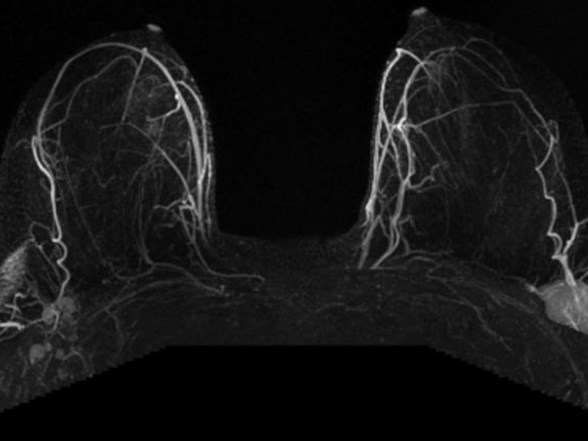

mrna asilari lenf bezi uzerinden uzun sureli koruma sagliyor

pfizer ve moderna nin asilari olunduktan sonra vucutta gozlemlenen sismenin nedeni ne euronews

biontech asisi sonrasi lenf bezi sismesi tehlikeli mi youtube